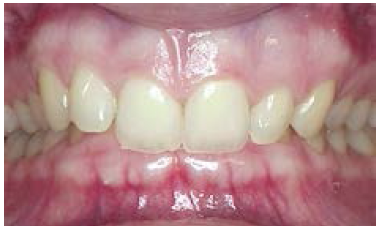

Figure 5. Anterior open bite.

Figure 5

Discrepancies: In a deep bite (overbite) (Figure 4), the maxillary incisors vertically overlap the mandibular incisors excessively. (In severe cases, mandibular incisors may contact the palate or maxillary incisor may strike mandibular gingiva.) In an open bite, there are areas where the maxillary and mandibular teeth do not touch. A patient can have an anterior or posterior open bite (Figure 5 and Figure 6). (An anterior open bite can sometimes be attributed to thumb sucking or a tongue thrust. Other times the condition is a skeletal problem.) Overjet refers to the distance between the facial surfaces of the maxillary incisors and the facial surfaces of the mandibular incisors.